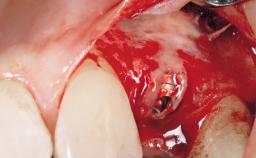

Late Flapless Placement of an Implant in a Maxillary Left Central Incisor Site

A 39-year-old male patient presented with a chief complaint of discomfort and gingival discoloration around his maxillary left central incisor. He was in good general health and was a non-smoker. His past dental history was significant because of the traumatic fracture of tooth 21 in a sporting accident at age 13. Initial dental treatment included endodontic therapy and a full-coverage restoration. The patient became symptomatic 5 years later, when structural failure of the tooth resulted in the dislodgment of the crown. Endodontic retreatment, apical surgery, and post-and-core restoration were performed.

Bone Augmentation Horizontal|Staged

Augmentation Materials Xenogenous|Membrane

Bone Volume Deficient horizontally, requiring prior grafting